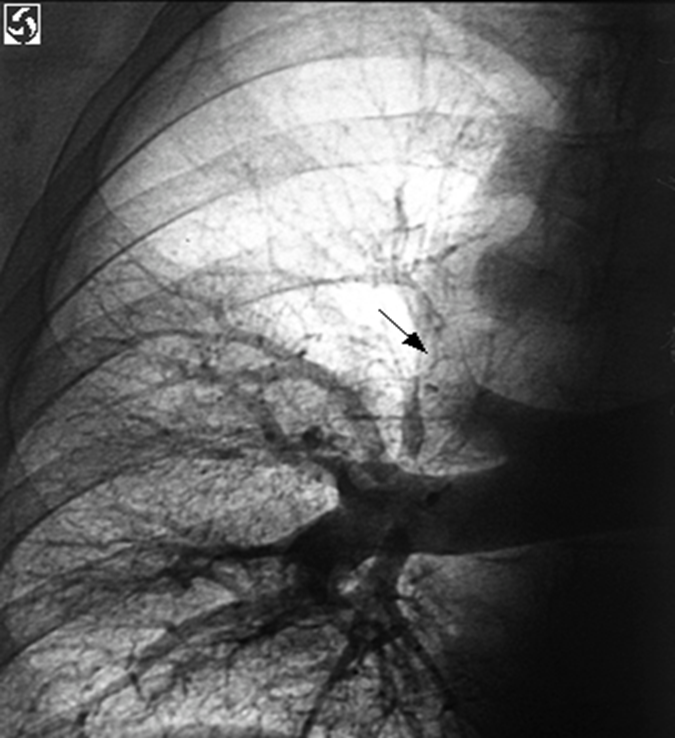

Pulmonary Angiography (GOLD STANDARD)

•Arrow indicates abrupt termination of a pulmonary artery.